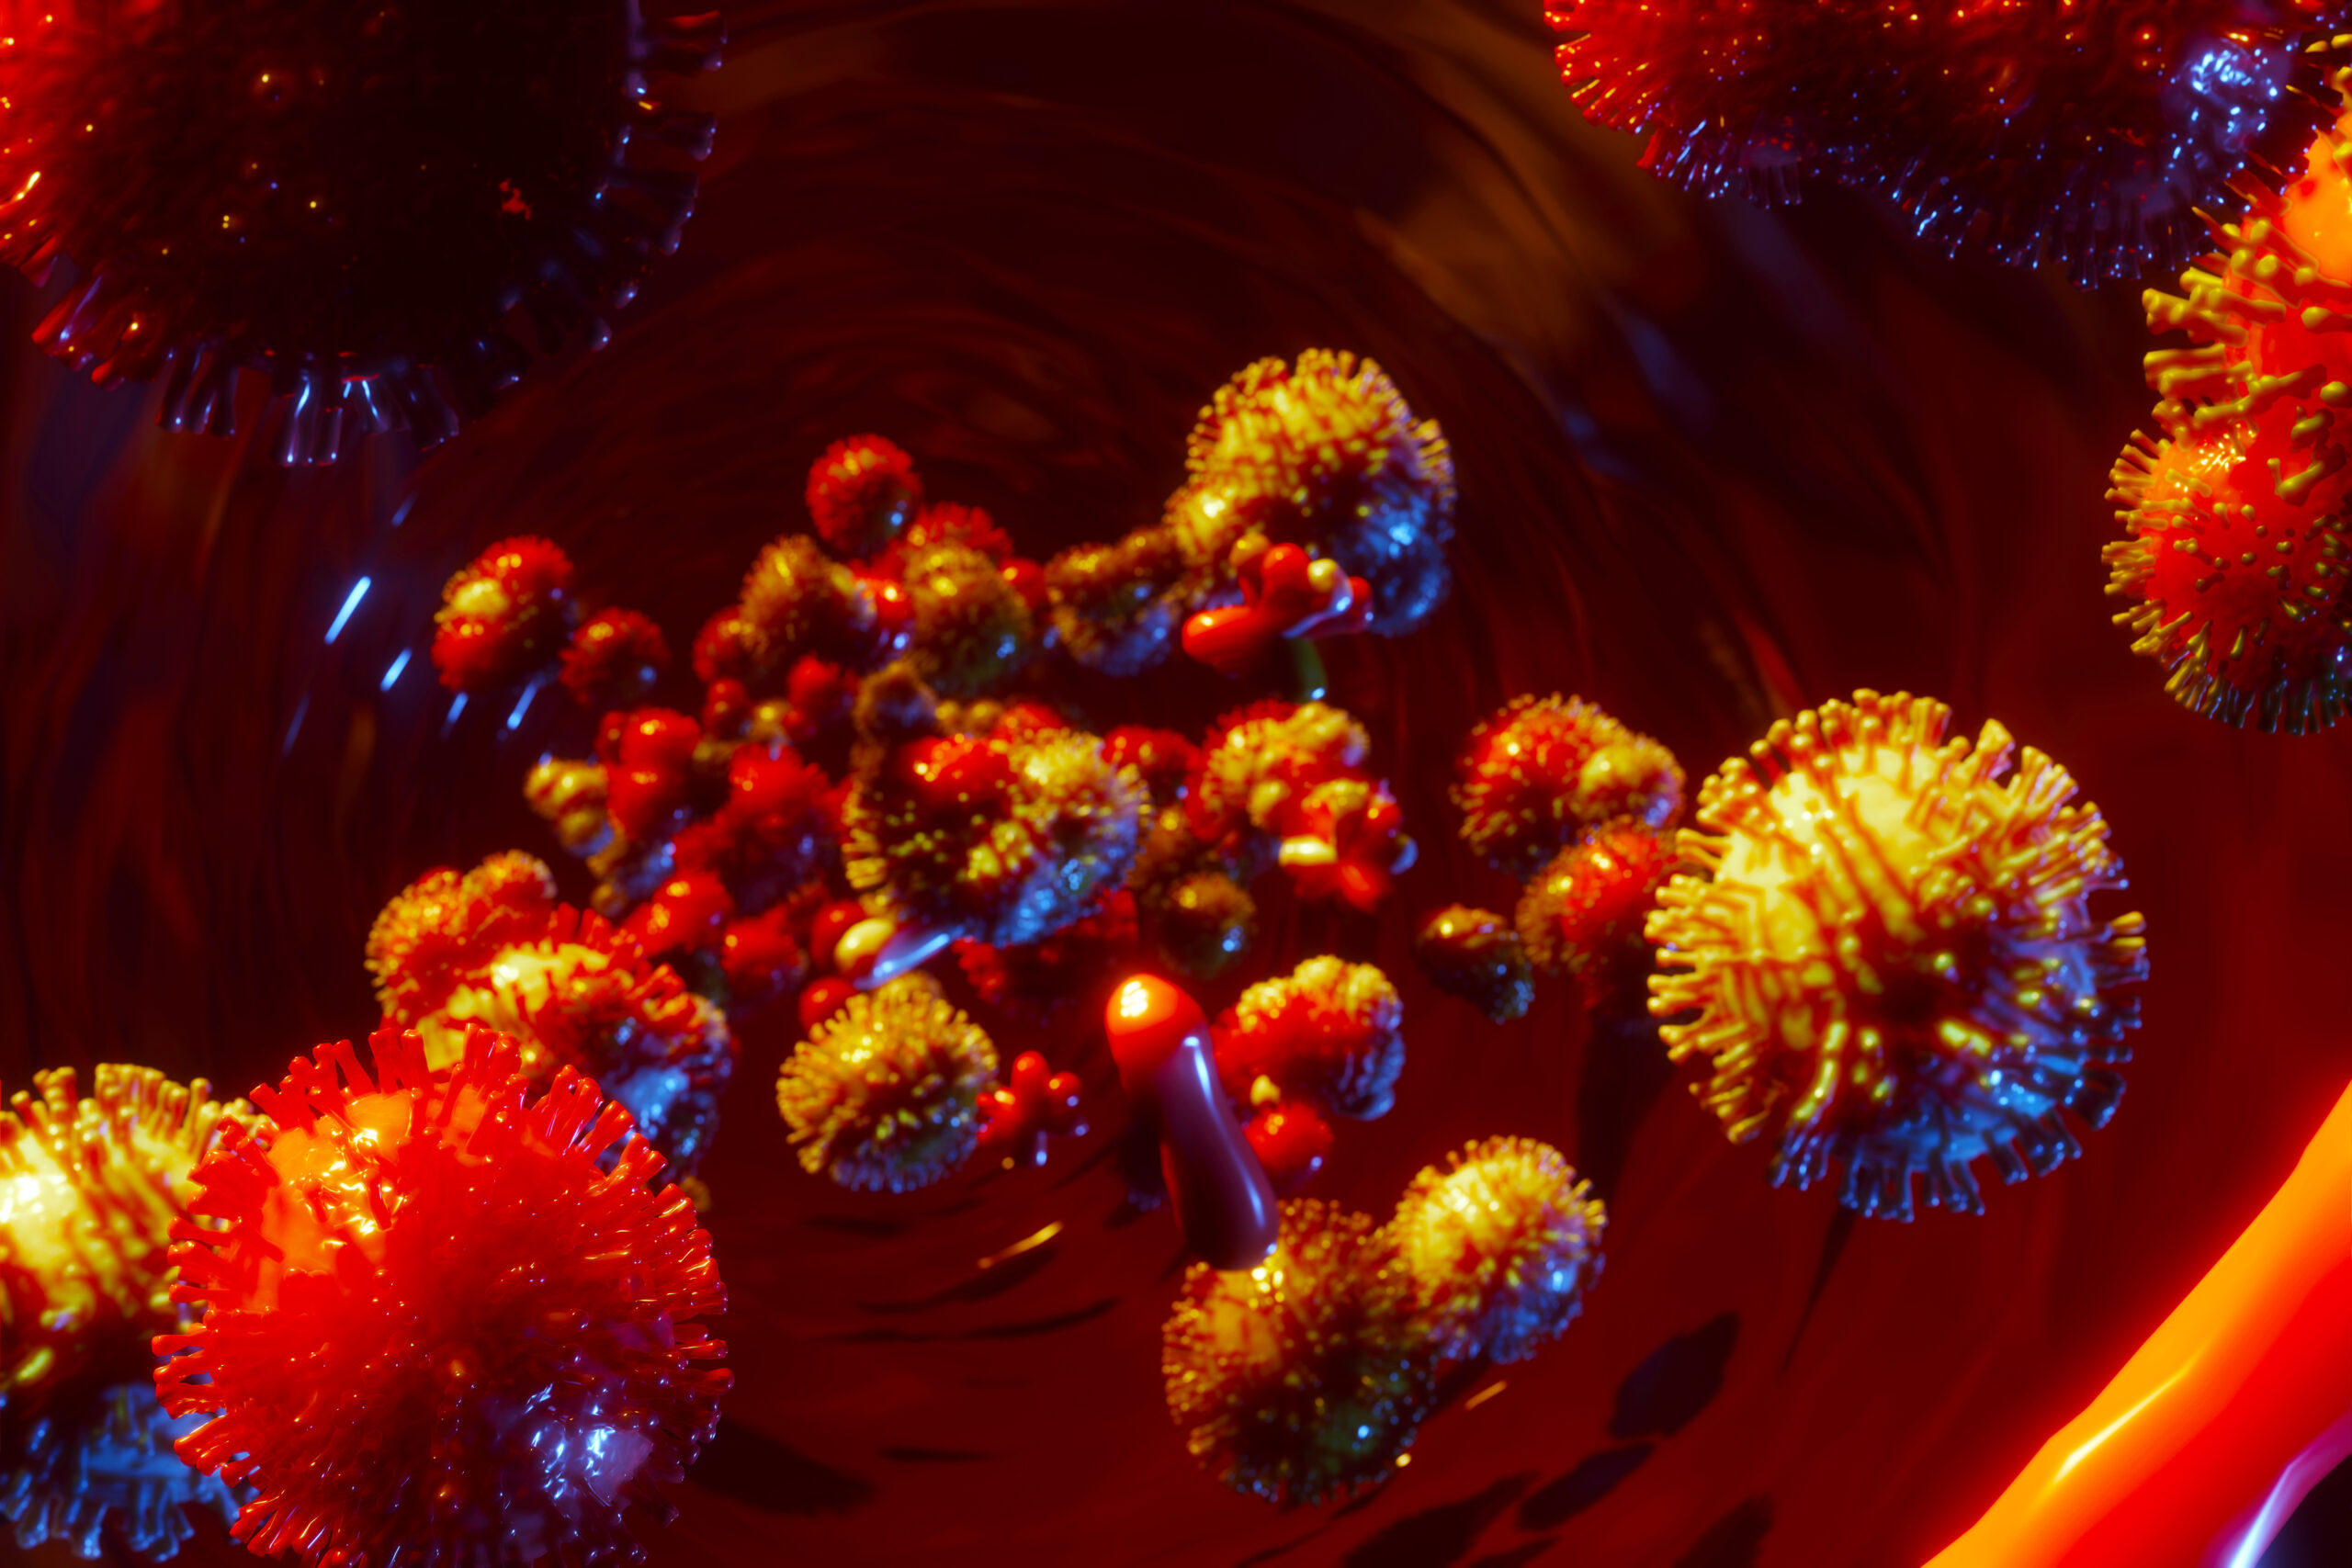

Investigadores del Conicet presentaron un suplemento dietario que alivia los síntomas del “Covid prolongado”

Un producto doblemente original, que puede ayudar a la salud de las millones de personas que todavía padecen las secuelas del Covid-19 acaba de ser presentado para su comercialización en Argentina.…